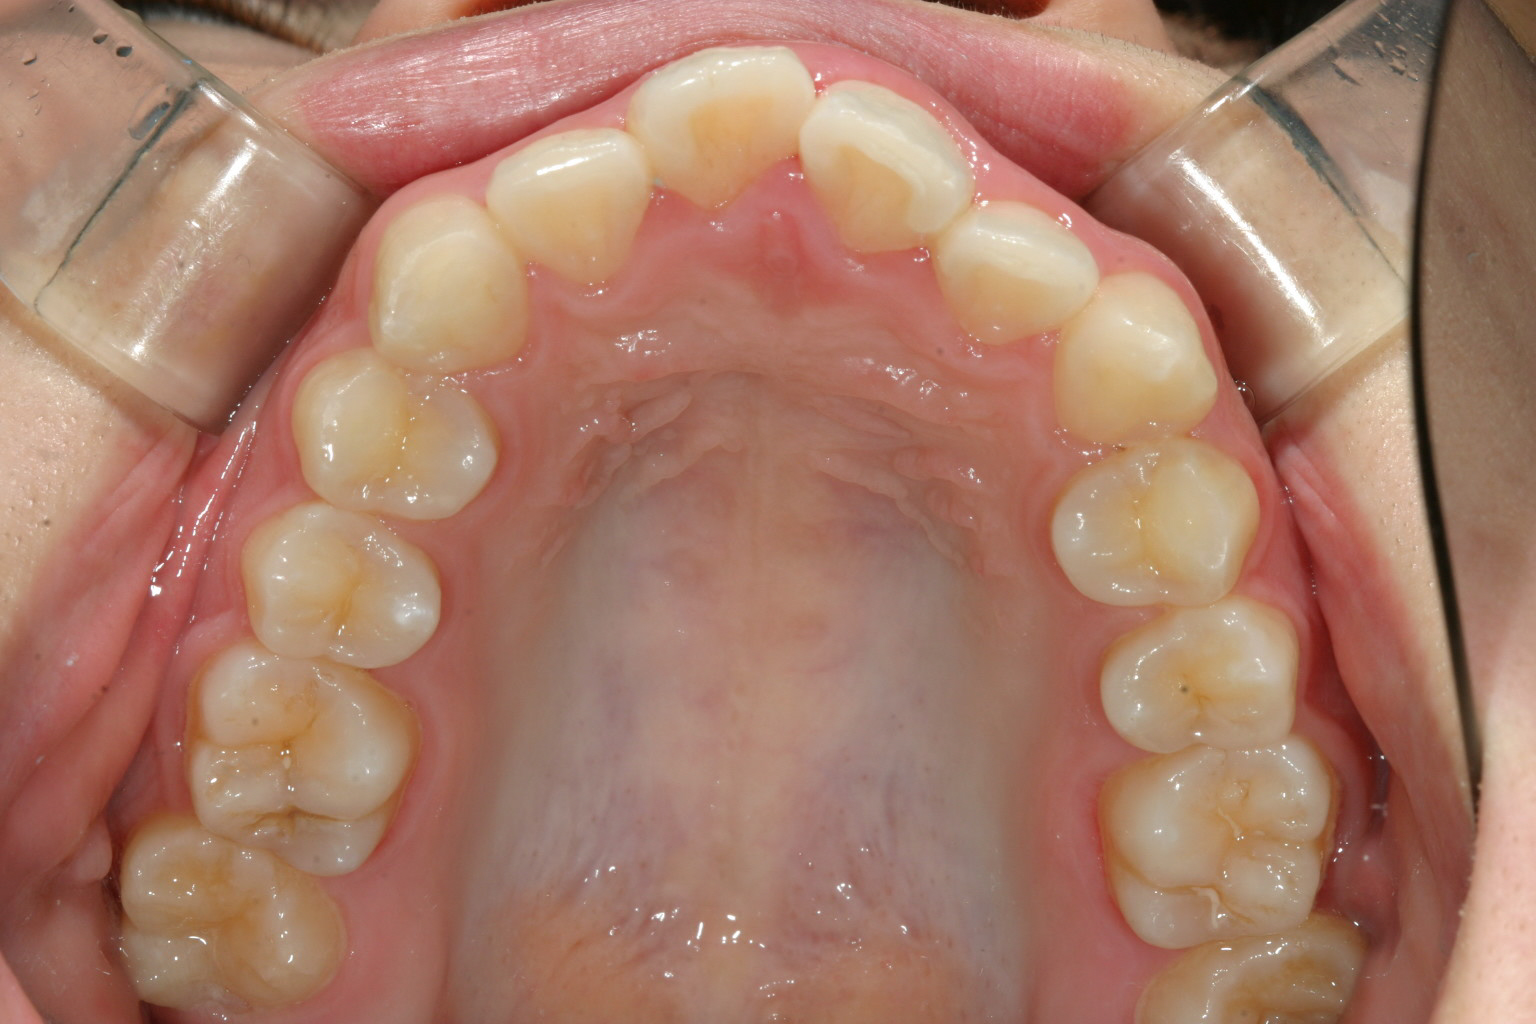

アーチが尖ってるのが気になります。

犬歯間を広げ尖ったアーチをU字に変えました。